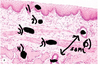

* Identify the following cell types

1. Chief cells (more eosinophilic)

2. Parietal cells